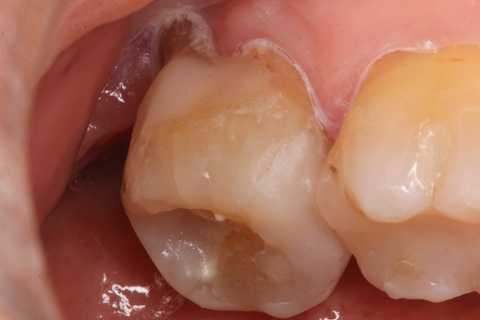

30代女性、左下7、Per、動揺度2.5

今日の症例は8年前に僕が親知らずが遠心に食い込んで虫歯になったものを神経を取らずにCR充填したものだが、とうとう接着剥がれが起こり神経が死んでしまった。神経は全く残っておらず。溶けてなくなっていた。

レントゲン写真では炎症は歯根周囲の歯槽骨に及んでいる。

この症例は歯根内部をいじられていないので、根管治療は難しくない。CRで歯冠を再建するのが難しかった。

再建が終わった後で、内部の治療をしてCRで埋め戻している。